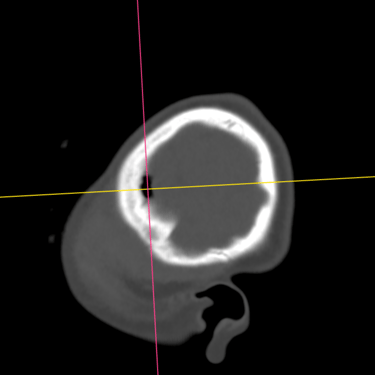

Fractura Craneal | Diagnóstico por Tomografía

La fractura craneal es una lesión que puede producirse tras un traumatismo craneoencefálico, con riesgo de comprometer el cerebro y las estructuras intracraneales. Los síntomas incluyen dolor local, edema, hematomas y, en casos graves, alteración del nivel de conciencia. La tomografía computarizada (TC) es el estudio de elección para su diagnóstico, ya que permite identificar con precisión el trazo de fractura, desplazamientos óseos, hemorragias asociadas y la afectación de senos venosos o base de cráneo. Un diagnóstico temprano mediante TC es esencial para definir la conducta terapéutica y prevenir complicaciones neurológicas potencialmente graves.